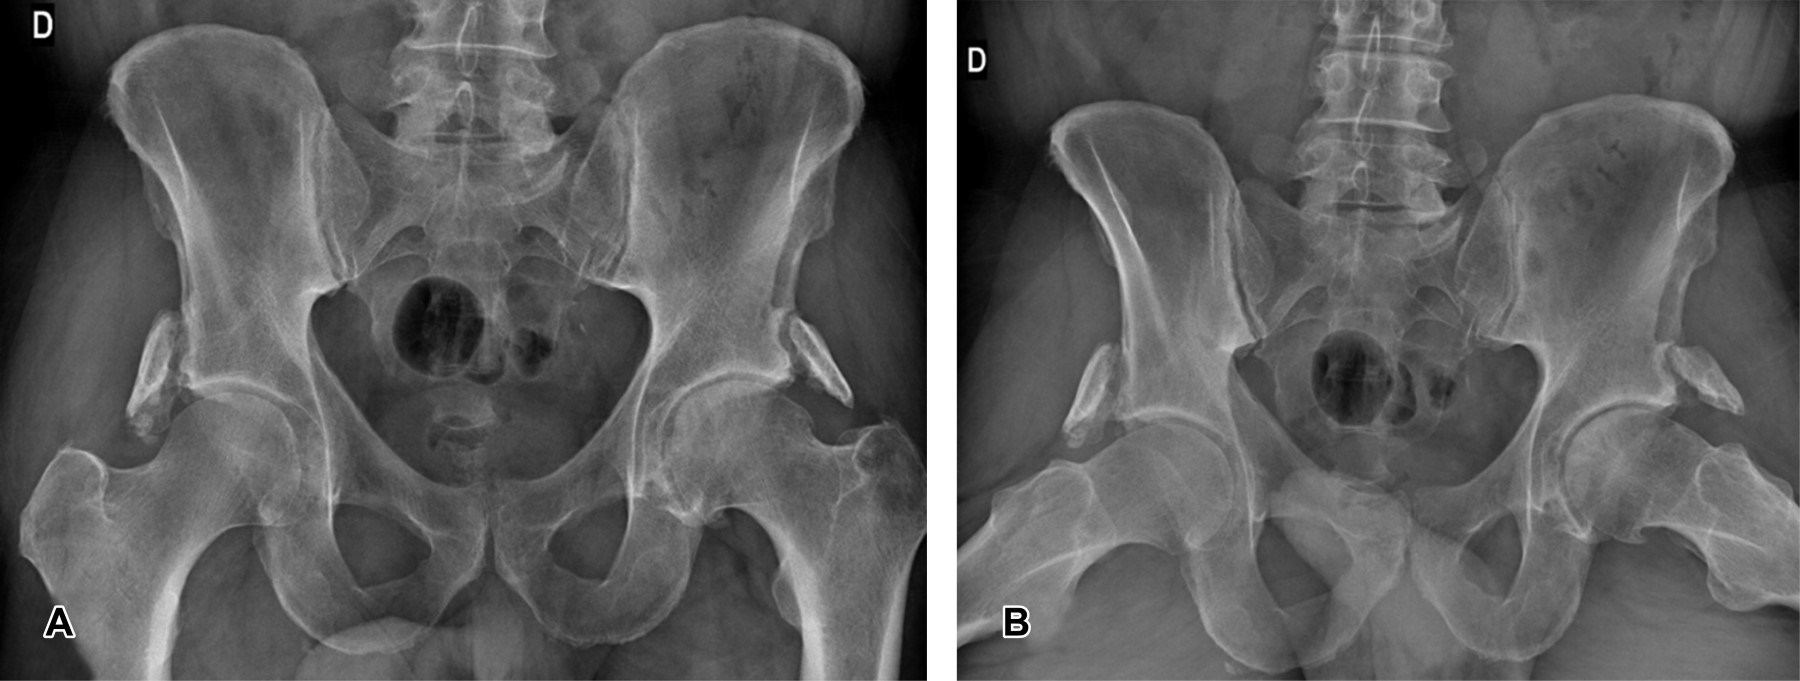

Mujer de 43 años de edad que acude con dolor articular sin traumatismo previo en la cadera izquierda de meses de duración. Se realiza una radiografía de pelvis anteroposterior (Figura 1) que pone de manifiesto la existencia de una estructura ósea lineal similar a una costilla o una falange, caracterizada por una cortical bien definida formando una o más pseudoarticulaciones con el hueso adyacente. Los hallazgos radiológicos son compatibles con la variante anatómica de la normalidad de costilla o dedo pélvico.

La localización más frecuente se observa en los tejidos blandos adyacentes al hueso iliaco o la articulación coxofemoral; sin embargo, puede localizarse alrededor del sacro, del cóccix o la sínfisis púbica. En la mayoría de las ocasiones es único y unilateral; no obstante, se han descrito casos de dedos pélvicos bilaterales y múltiples como es el caso del paciente aquí presentado. El manejo de estos pacientes es quirúrgico únicamente si se confirma que la lesión es la causante de dolor.

Figura 1